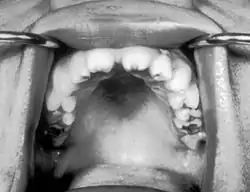

أسنان هتشنسون (بالإنجليزية: Hutchinson's teeth) عبارة عن أسنان غير طبيعية تكون مثلمة على حافتها الحرة وهي علامة طبية لمرض يدعى الزهري الخلقي.[1]

أسنان هتشنسون